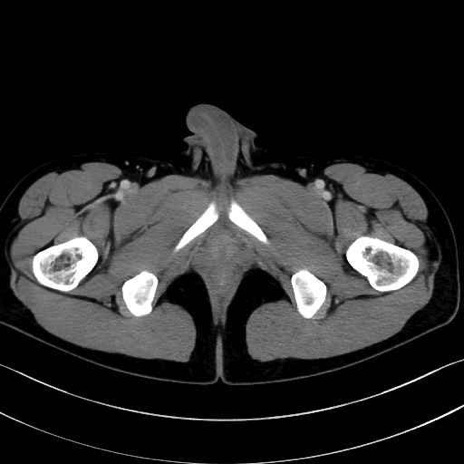

5. 大腿前面(大腿四頭筋群・伸筋群)

縫工筋 (Sartorius)

大腿直筋 (Rectus femoris)

外側広筋 (Vastus lateralis)

中間広筋 (Vastus intermedius)

6. 大腿内側(内転筋群)

恥骨筋 (Pectineus)